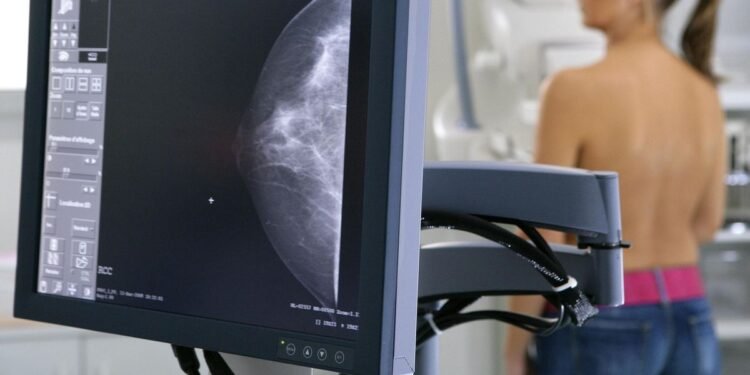

El Ministerio de Salud de la provincia de Buenos Aires ha establecido una nueva normativa que reduce de manera significativa la edad para la realización de la primera mamografía. A partir de ahora, las mujeres podrán acceder a este examen a los 40 años, una diferencia de 10 años respecto a la recomendación anterior de realizarlo a partir de los 50 años. Este cambio implica una frecuencia bienal de las mamografías hasta los 75 años, siempre bajo criterio médico.

La implementación de esta nueva indicación está respaldada por el Instituto Provincial del Cáncer (IPC) y cuenta con el apoyo de diversas sociedades científicas. Estudios indican que la detección temprana del cáncer de mama permite que hasta el 90% de los casos sean tratados con éxito. Este cáncer es el más frecuente a nivel mundial, y en Argentina se diagnostican aproximadamente 360 nuevos casos diarios, de los cuales 60 se registran en la provincia de Buenos Aires.

El gobierno bonaerense ha reforzado su sistema de salud pública para mejorar el acceso a diagnósticos y tratamientos, incorporando 22 nuevos mamógrafos en hospitales públicos. A la fecha, la provincia cuenta con un total de 187 mamógrafos, lo que permite una mayor disponibilidad para la población. La directora del IPC, Marina Pifano, subrayó que el objetivo es aumentar las tasas de detección temprana, enfatizando que el pronóstico del cáncer de mama está íntimamente ligado al momento en que se descubre.